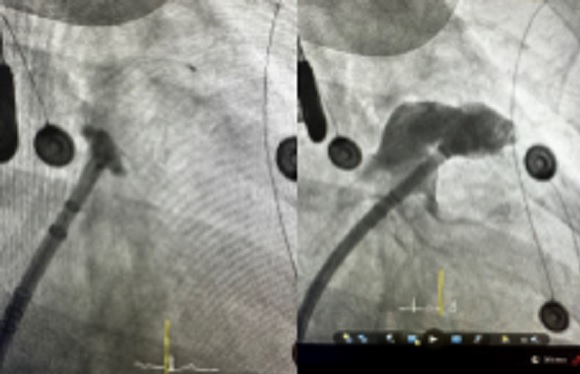

Ακτινοσκοπική λήψη από την τοποθέτηση του καθετήρα κατάλυσης (FARAPULSE™ Pulsed Field Ablation System) στο στόμιο της αριστερής άνω πνευμονικής φλέβας,

Σκιαγράφηση του ωτίου του αριστερού κόλπου